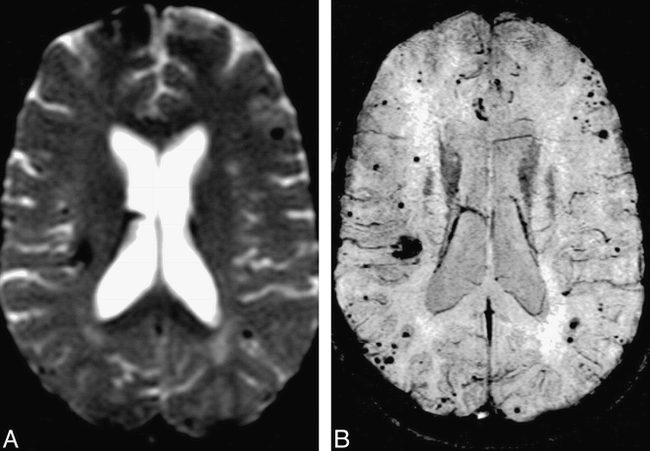

Comparison of HRBV and T2*-weighted images.

A, T2*-weighted echo-planar image (TE, 40) shows the susceptibility effects of multiple cavernomas. Susceptibility is present in the right frontal region.

B, HRBV image shows numerous additional lesions. Note that the margins of the cavernomas are defined better with this technique.